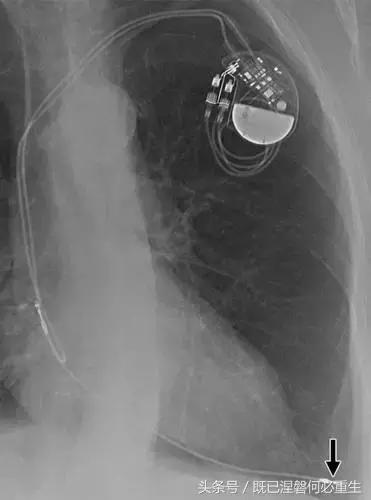

图5C,70岁女性心室穿孔。 正位胸片显示,圣犹达医疗双室起搏器的RV导联(箭头)超出心室轮廓。 心肌穿孔很少会导致放血或压塞。 患者没有受到并发症或随后的铅改变的不良影响(修订电极显示)。 心室穿孔可能导致对膜片的不适当刺激。